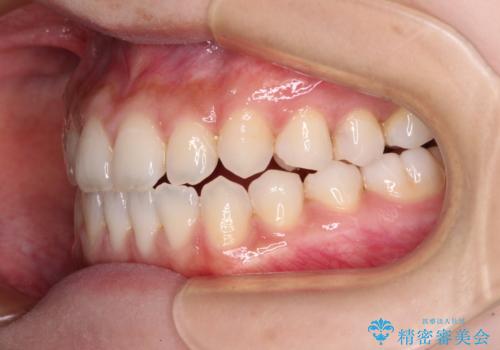

舌突出癖で口元が開いてしまう 舌トレーニングを行ったインビザライン矯正

- 前歯の上下スペースと前歯の隙間を気にして来院された患者様です。

インビザラインにより上下の前歯の隙間を閉じていくこととしました。

上下の隙間に舌が入り込むことが、すきっ歯やオープンバイトの原因であったため、舌の筋肉のトレーニングも並行して行い、後戻りの抑制を図りました。